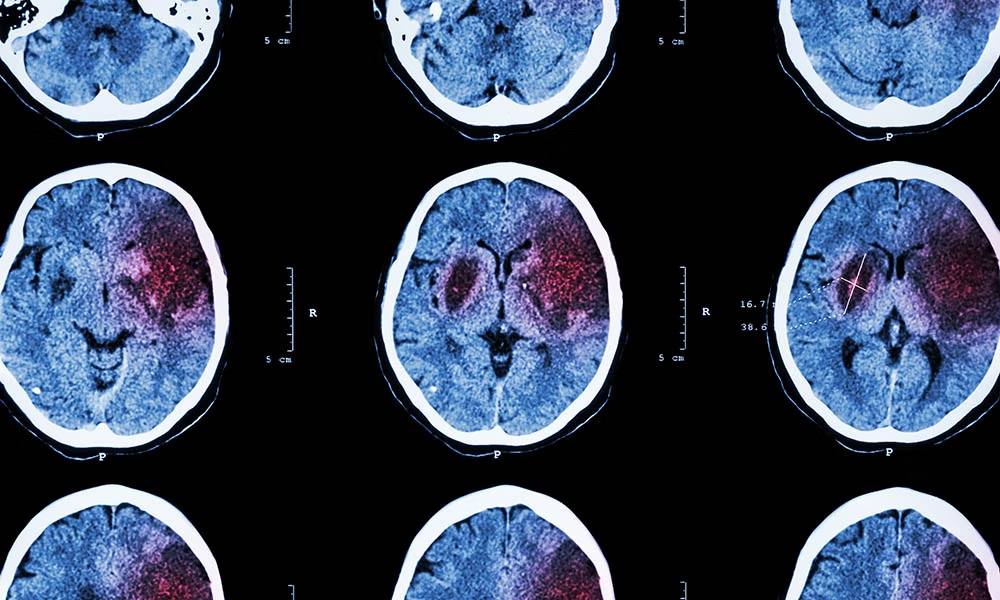

為了確保有針對(duì)性的治療,有必要確定患者是否患有血流量減少或腦出血。這通常通過(guò)成像技術(shù)來(lái)完成,例如大腦的計(jì)算機(jī)斷層掃描 (CT) 和/或磁共振成像 (MRI)。

中風(fēng)期間,大腦的血液供應(yīng)受損。根據(jù)中風(fēng)的持續(xù)時(shí)間和程度,受影響區(qū)域的細(xì)胞可能會(huì)受損甚至死亡。根據(jù)中風(fēng)的嚴(yán)重程度和部位,它可能會(huì)導(dǎo)致功能障礙甚至死亡。

腦梗塞(缺血)

腦出血(出血性中風(fēng))

腦出血涉及血液流入周圍的腦組織。由此產(chǎn)生的壓力可能會(huì)對(duì)未受影響的大腦區(qū)域造成額外的損害。這種腦內(nèi)或腦外出血可能是由高血壓(高血壓)、凝血障礙、血管炎癥(血管炎)、腫瘤或血液稀釋劑(抗凝劑)不當(dāng)?shù)乃幬镏委熞鸬摹?/p>

腦出血

中風(fēng)會(huì)破壞大腦的血液供應(yīng)(由于血流量減少或腦出血)。除臨床神經(jīng)學(xué)檢查外,還通過(guò)影像技術(shù)(CT、MRI)進(jìn)行診斷。